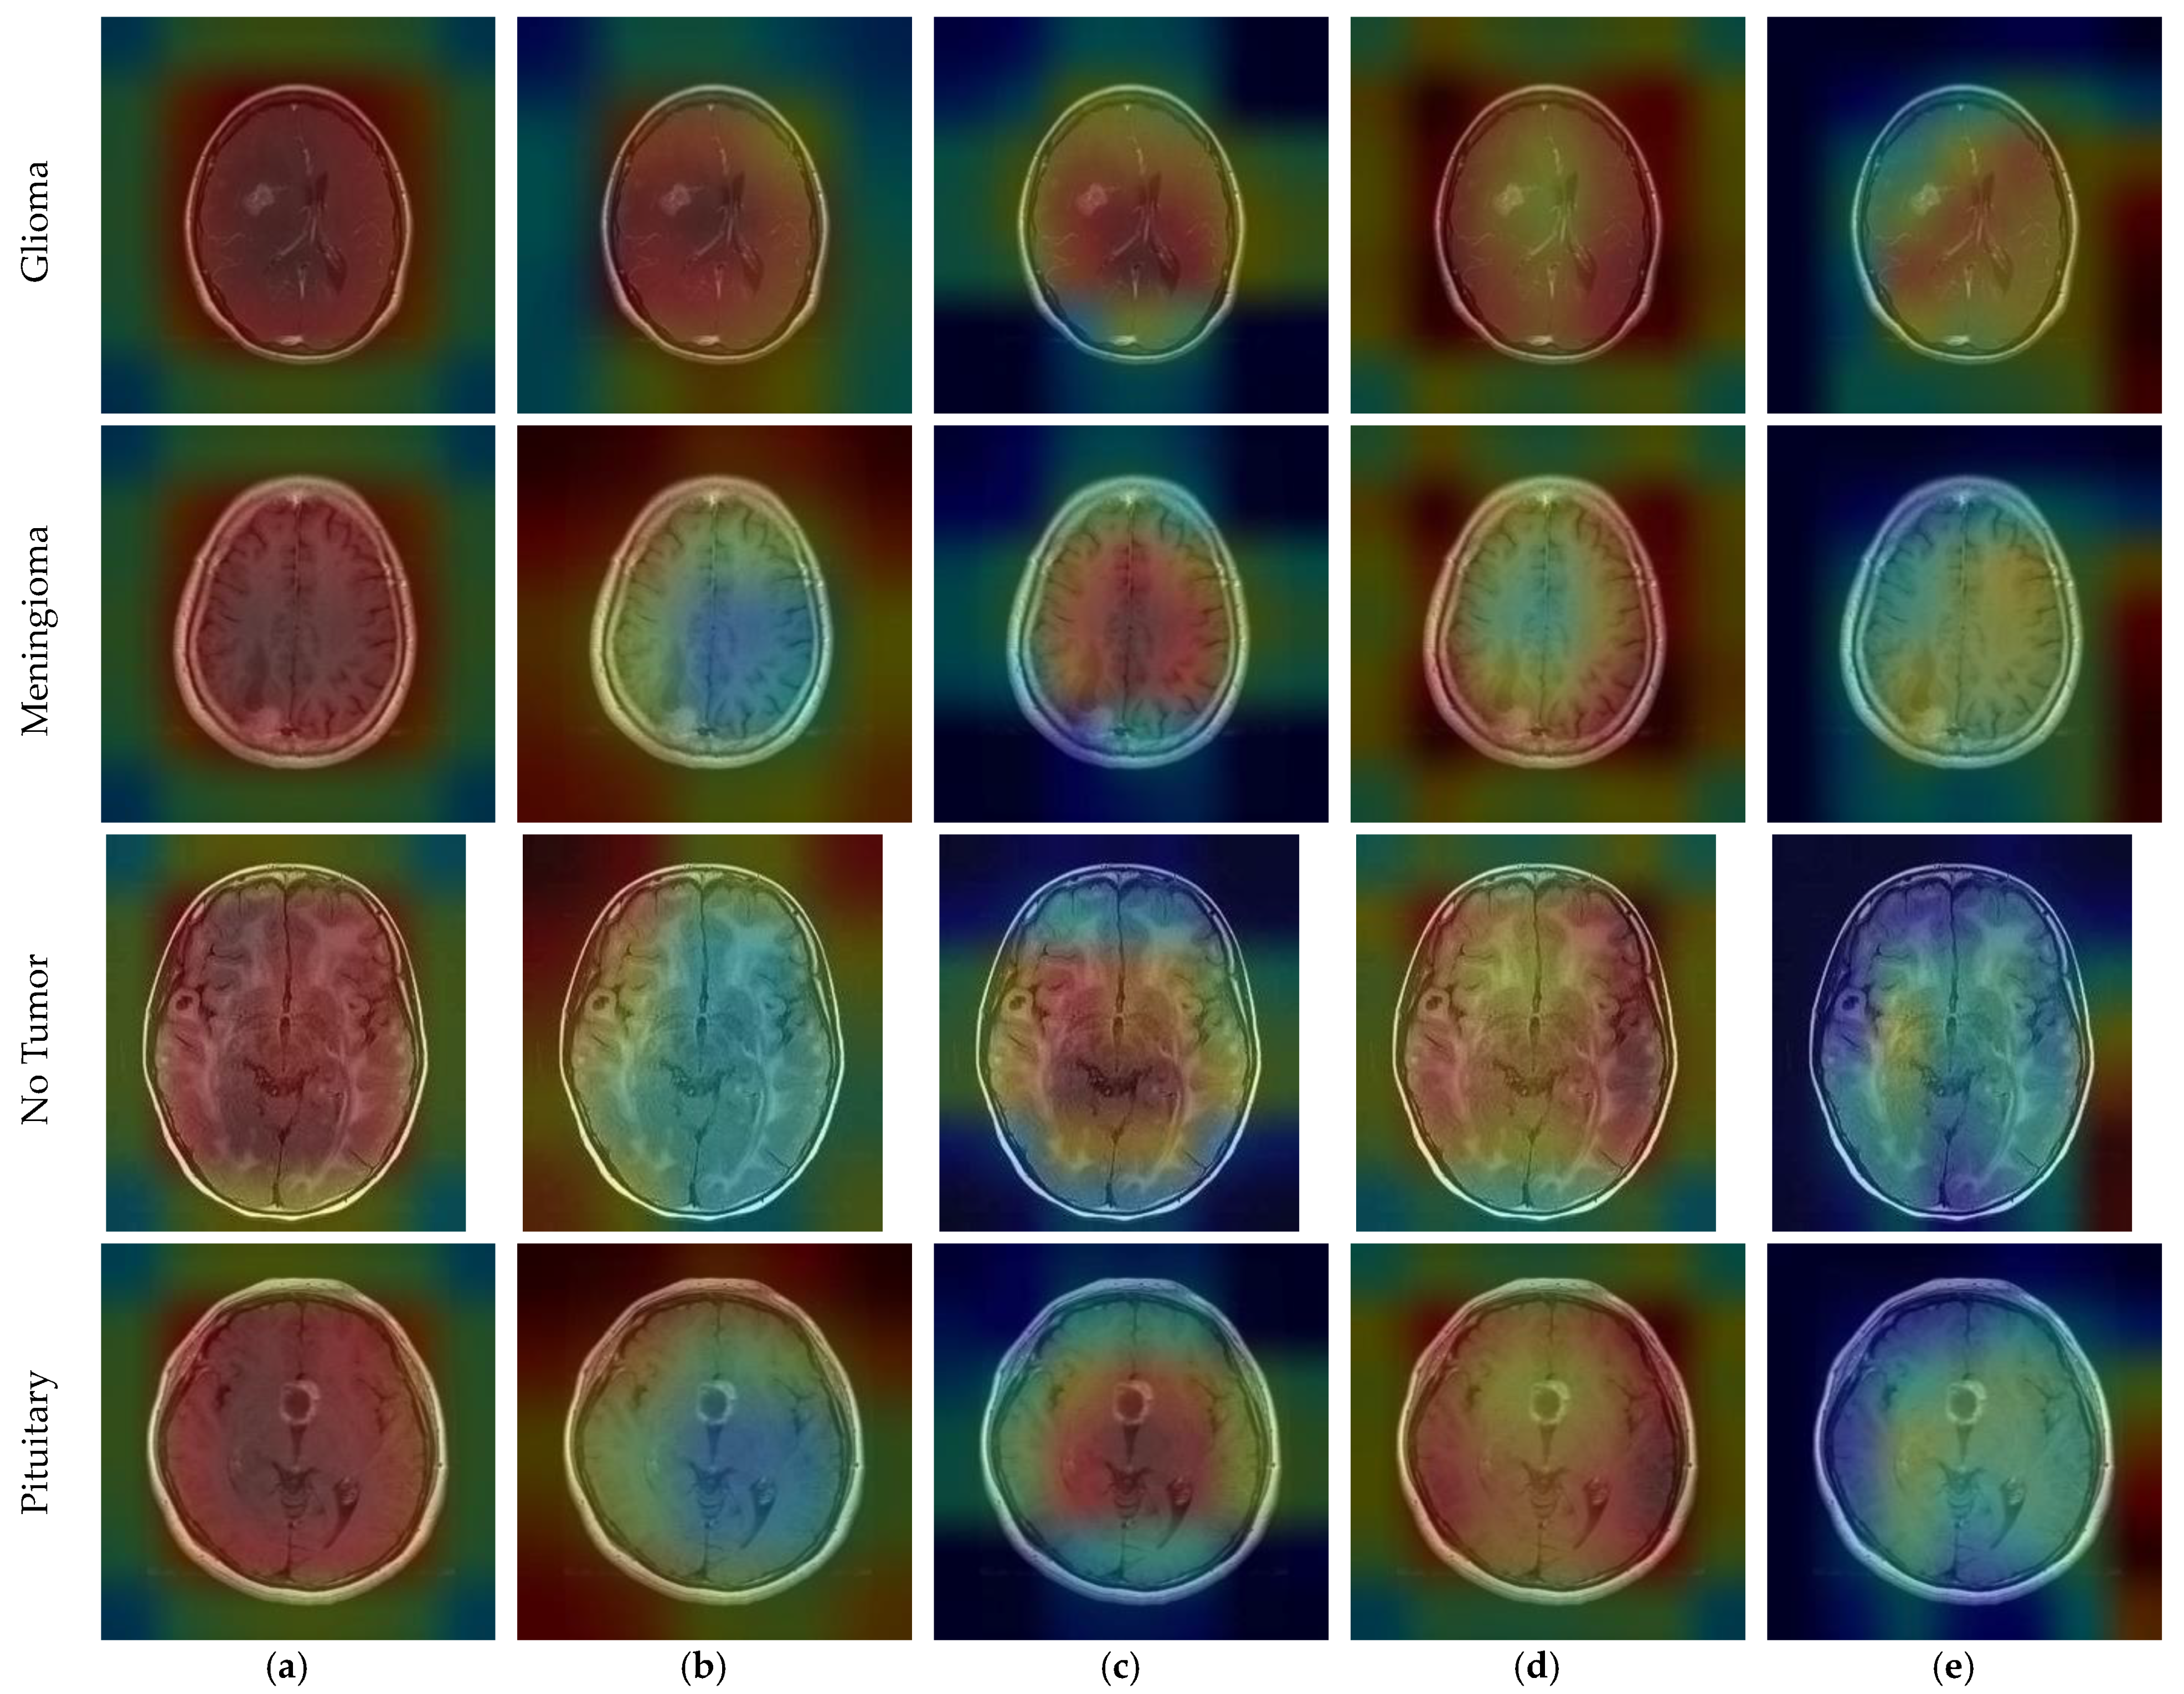

CNN outputs visualized on a heat map with Grad-CAM for Dataset 1, Dataset 2, and Dataset 3 are represented in Figure 10, Figure 11 and Figure 12, respectively. The original images are overlaid with a color spectrum ranging from blue to red, where the red regions indicate the dominant focus during model predictions. The sample images in Figure 1 were used as the original images in the Grad-CAM application. Grad-CAM analyses of the models in the ensemble framework are presented for three data sets. Figure 10 shows that while all models focus on the brain, different models may focus on different regions of the same MRI image. This trend also helps to increase feature diversity. This can be considered an indicator of better performance with ensemble learning.

Figure 12.

CNN outputs visualized on a heat map with Grad-CAM for Dataset 3: (a) DenseNet201; (b) InceptionResNetV2; (c) MobileNetV2; (d) RegNetX008; (e) ResNet101.